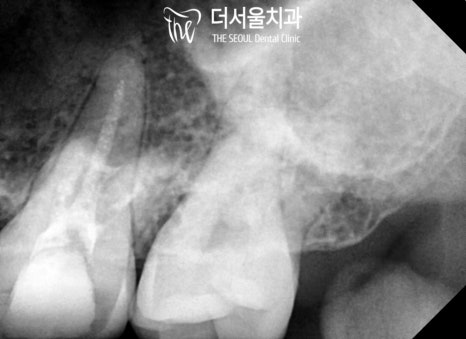

위쪽도 교정 전 신경치료 를 도왔습니다.

위쪽이라 접근하는데 어려움이 있긴 했지만

끝까지 꼼꼼하게 밀폐 작업을 도운 뒤

모든 과정을 마무리했습니다.

코어를 튼튼하게 만들어주고,

보철까지 제작하여 올려드렸는데요.

건강하고 깔끔한 모습의

어금니가 씌워져 있네요ㅎㅎ

다행히 환자께서도 욱신거리고

아픈 느낌이 하나도 들지 않는다며

결과에 대해 마음에 들어 하셨는데요.